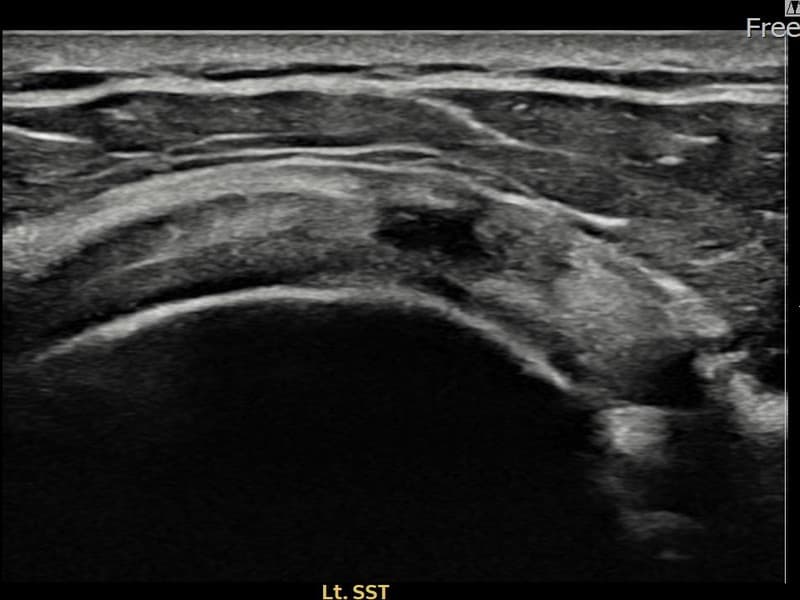

术前

术前超声确认左侧 冈上肌腱 关节面侧部分撕裂,左侧冈上肌腱回声不连续伴肌腱缺损(8mm × 3mm (肌腱厚度约33%缺损))。术后超声显示撕裂部位充满再生组织,肌腱连续性恢复,回声模式正常化。